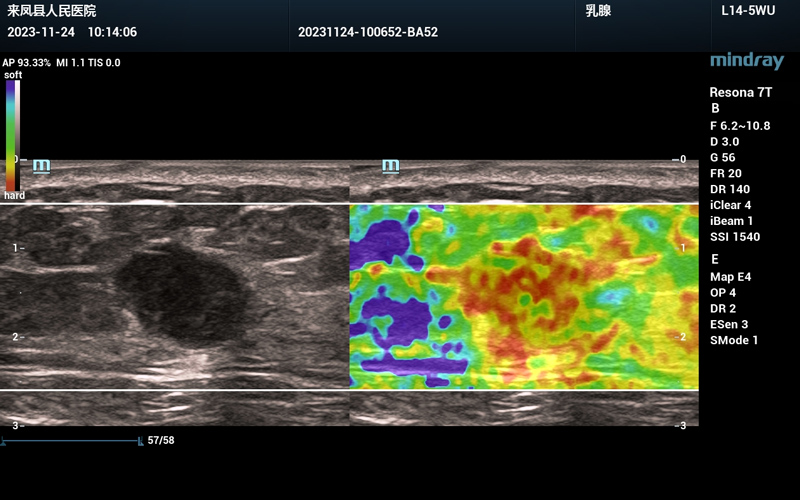

简单来说,应变弹性成像评分法基于肿块内的颜色分布比例进行评分,从红色至蓝色代表组织的硬度由硬至软,若乳腺肿块内红色区域比例较大,代表结节越硬,恶性的概率也会增大。与传统B超相比,超声弹性成像能够更清晰的提示乳腺是否组织符合恶性表现。(参考下图,蓝色区域的硬度小,红色区域的硬度高)。

乳腺组织的应变弹性成像图